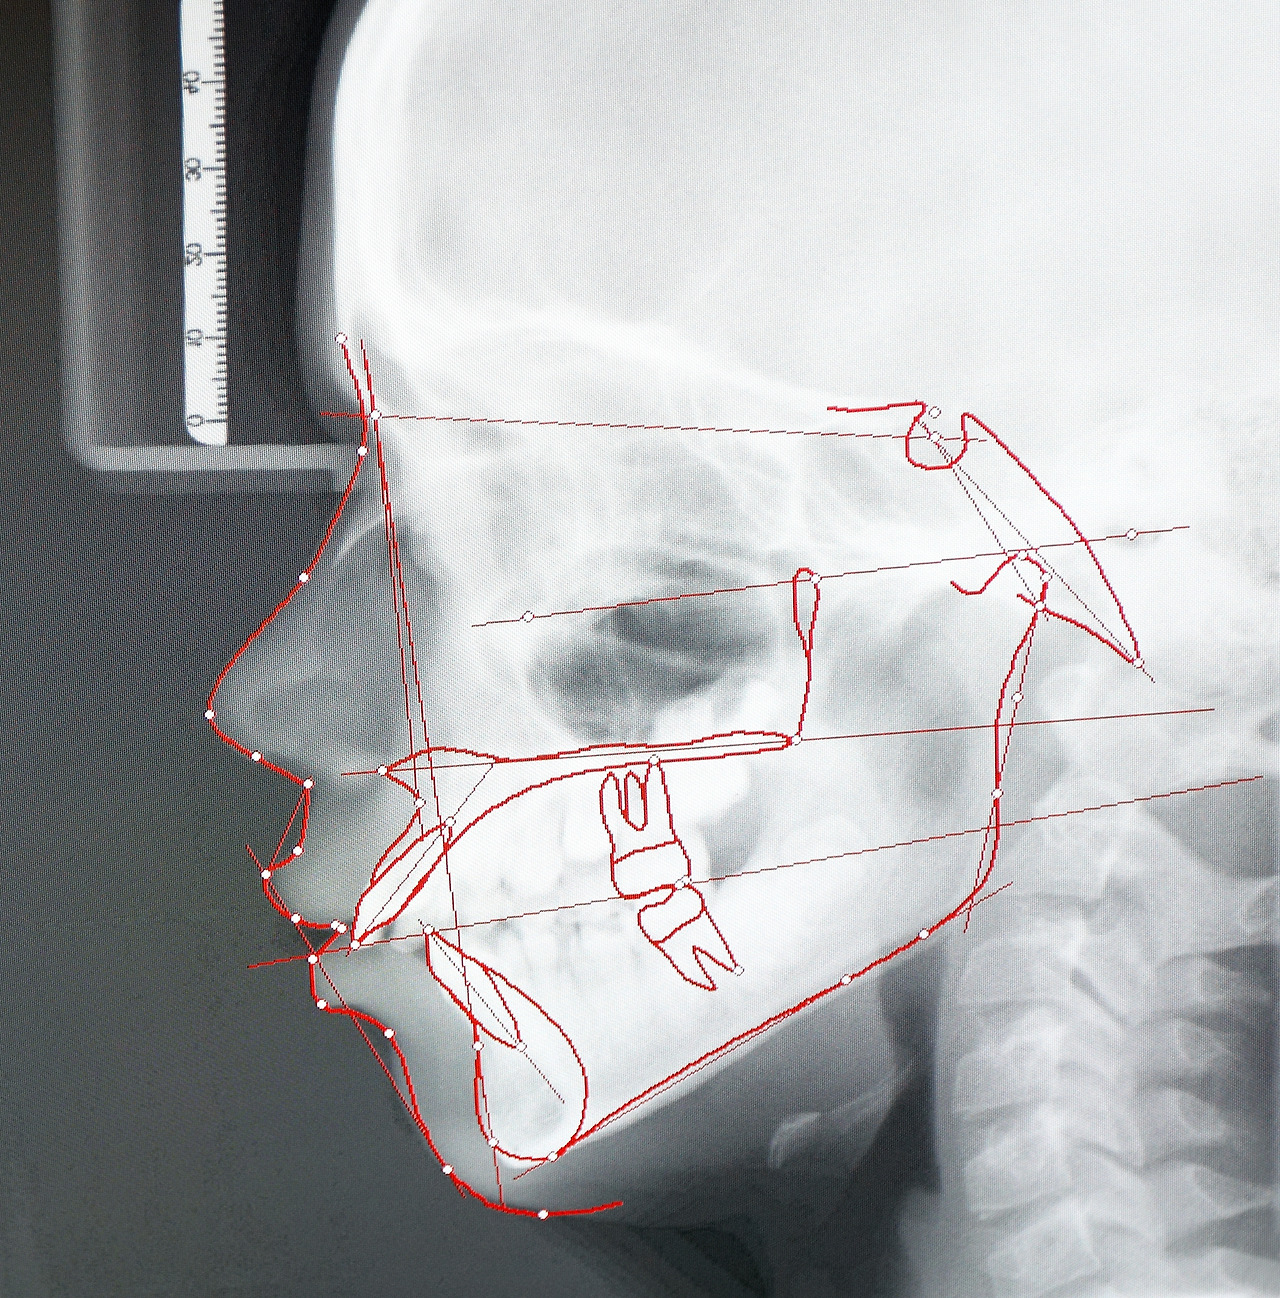

턱관절은 아래턱뼈, 머리뼈, 그 사이의 턱관절 관절원판인 디스크, 인대, 주위 근육 등을 통틀어 이르는 말로 주로 입을 벌리거나 다물 때, 턱을 전후 좌우로 움직일 때 사용하는 관절입니다.

관절 주변에 근육염이 있거나 턱관절이 원래 있어야 할 위치에서 벗어나 앞쪽으로 튀어나오면서 관절 뒤쪽이 자극을 받아 통증이나 부종이 생겨 턱관절 장애가 나타날 수 있습니다.

턱관절에 문제가 생기면 턱 주변의 신경과 한 곳에서 만나는 머리·어깨 주변의 신경에도 영향을 미쳐 두통이나 이명, 어깨 통증이 발생하게 됩니다.